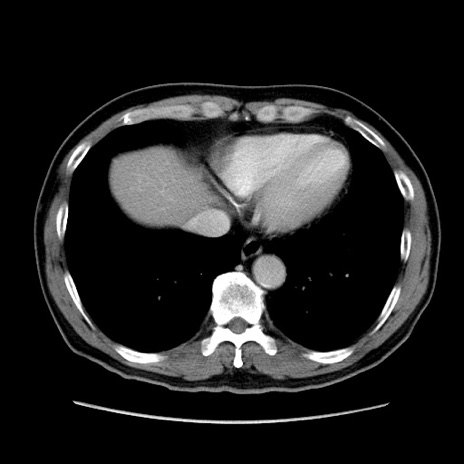

冠状断像

矢状断像